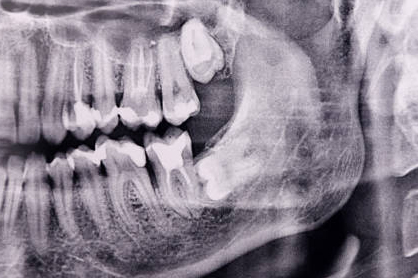

Difficult Cases

- We treat patients when other providers cannot manage.

Severe Bone Loss